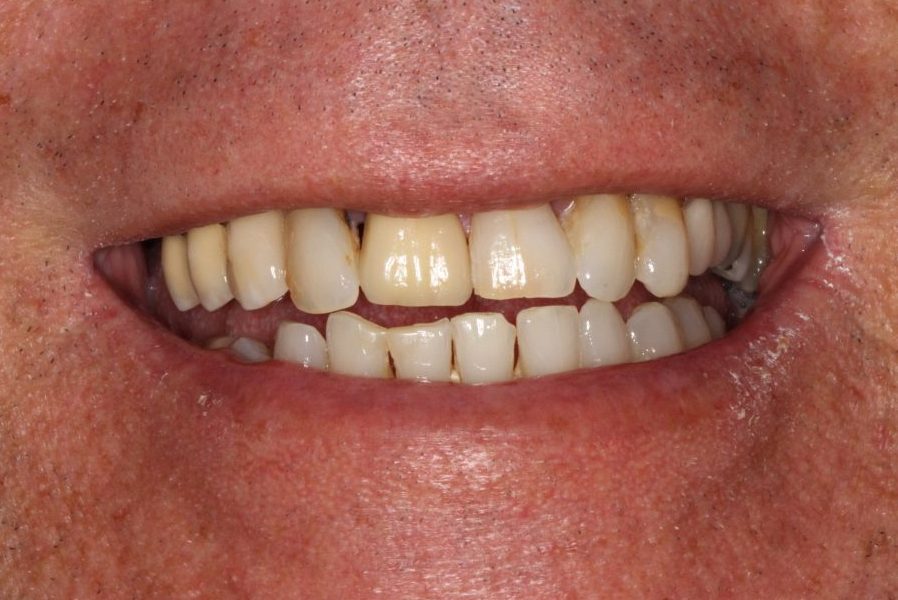

Lenny

Full Mouth Reconstruction with Upper & Lower Arch Replacement

“Lenny presented with advanced periodontal disease which was causing extensive bone resorption and tooth mobility. His teeth were getting loose and general dental health was poor. Eventually he suffered with a severe gum infection that caused him excruciating pain and stress. Lenny was extremely fearful of the dentist and the fact that PGA Dentistry offered IV sedation was a huge benefit.”

Advanced periodontitis leading to bone resorption & tooth mobility.